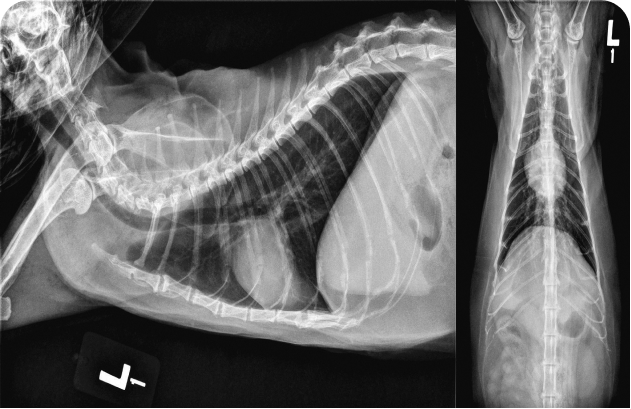

«При клинически нестабильном состоянии или респираторном дистрессе вначале следует стабилизировать функцию сердца, и только затем выполнять диагностические исследования; возможным исключением может быть срочная рентгенография органов грудной полости».

У котят шумы в сердце обнаруживают относительно часто, и при их диагностике и лечении врач должен придерживаться систематического подхода. Решающую роль в определении следующих шагов играют тщательный сбор анамнеза и тщательное клиническое обследование. Рентгенография грудной клетки может быть полезна при первоначальном обследовании, но для установления окончательного диагноза причин шума требуется эхокардиография; показанием к ее проведению считают шумы IV степени или выше, либо клинические признаки по результатам физикального осмотра. Терапию определяют исключительно на основании окончательного диагноза.